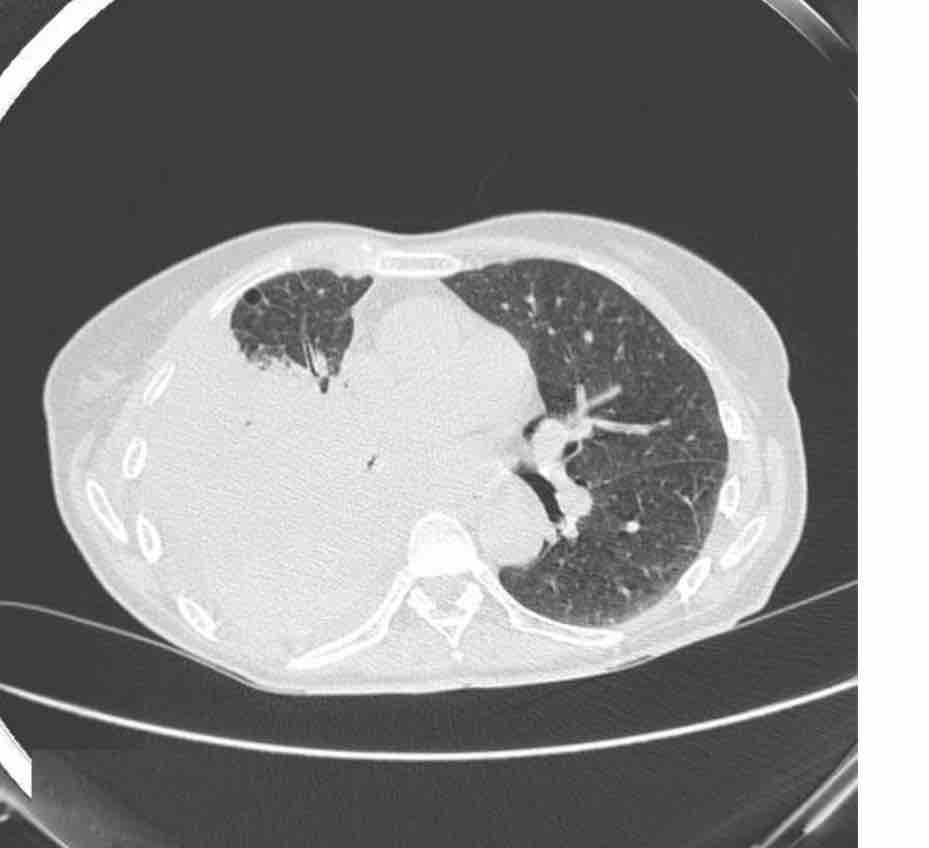

Sus problemas de salud comenzaron en abril de este año, con lo que se pensó que era una tos, para mayo ya era claro que el problema era mayor. Se le realizó en junio un TAC de Tórax que reveló un tumor y lo que ya parecía ser cáncer. Sin embargo, lo complicado de la zona evitó que al momento de obtener una prueba de tejido se pudiera diagnosticar correctamente con una biopsia, un segundo examen reveló la enfermedad.

Her health problems began in April of this year, with what was thought to be just a cough, by May it was already clear that the problem was greater. She underwent a chest CT scan in June that revealed a tumor and what already seemed to be cancer. However, the complexity of the area prevented her from being able to be correctly diagnosed with a biopsy at the time of obtaining a tissue test, a second examination revealed the disease.